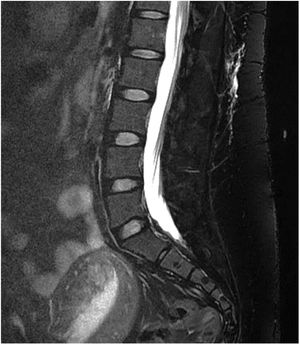

- -

Gadolinium-enhanced spinal MRI: a fat-suppressed T2 sequence should be included. Images may show pachymeningeal enhancement, dilated nerve root sheaths, engorged epidural venous sinuses, or meningeal diverticula.50,62 In addition to indirect signs of SIH, spinal MRI may also be useful in locating the CSF leak, with the observation of fluid collections in the epidural soft tissues (Fig. 3), which are generally non-compressive (60% of cases).59 Therefore, spinal MRI should always be performed simultaneously with brain MRI if SIH is suspected.59